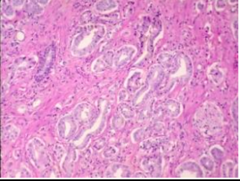

Papillary

Exophytic growth pattern with fibrovascular cores supporting proliferative epithelium Cauliflower or coral shaped structures with branching fibrovascular core